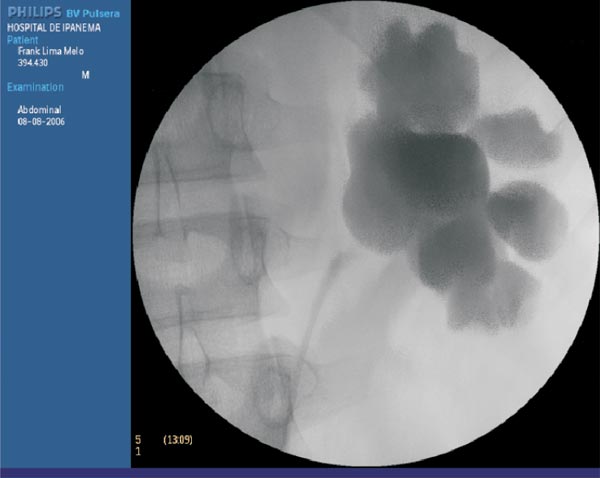

With the patient in lithotomic position, a cystoscopy is performed with the accomplishment of a retrograde ureteropyeloghaphy (Photo 1). Afterwards, a 7 F ureteral catheter is inserted with one tip placed bellow the ureteropelvic junction and the other outside the urethra connected to an 8 F Levine catheter. (Figure1).

Photo 1 - Retrograde pyelography performed before the procedure depicting the ureteropelvic junction because of an aberrant vessel.